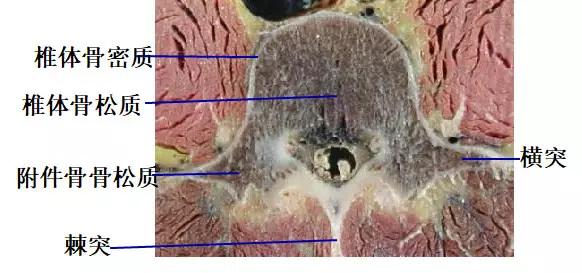

CT片所见骨质结构

椎体、椎板、椎弓根、关节突、横突、棘突。

CT断层表现

1.脊椎及附件骨

骨皮质: 位于椎体及附件的边缘部,CT表现为致密、连续的线状或带状影。

骨松质:位于骨结构的中央部,CT表现为细密的网格状影,边缘清楚。